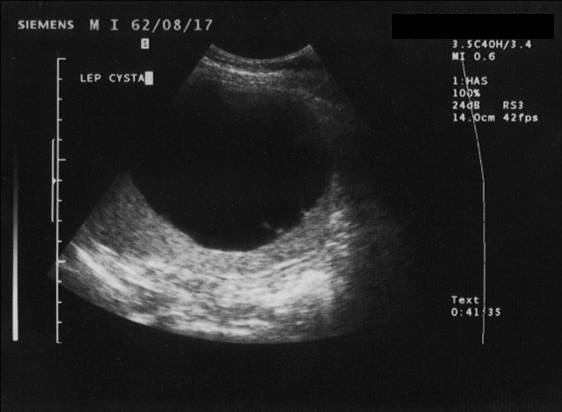

14.1.4.1.1. Cysta

Typical appearence includes a well defined, anechogenic fluid-containing lesion with sharp margin. Usually thin septa can be included and wall calcification can be observed as well. Their size varies between 3 mm and 10-12 cm.

The simple cyst (Figure 16) indicates a difference from the multicystic liver only in the number of the cysts. Conversely, the polycystic liver (Figure 17) is an autosomal dominant inheritant disorder, in which the cystic conversion can be present in up to 70-80% of the liver parenchyma due to the large number of the cysts. It often accompanies with polycystic kidneys, whilst the entire polycystic syndrome – if also polycystic affection of the pancreas is also associated – occurs very rarely.

Figure 16: Simple liver cyst, US